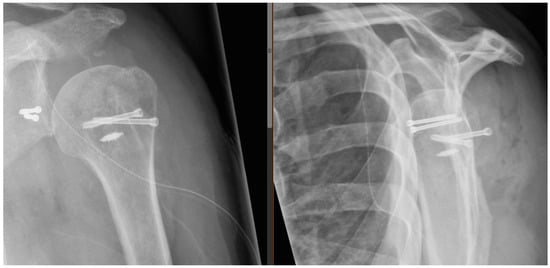

Postoperative radiographs and CT scans obtained one day postoperatively showed good positioning of all the bony fragments, and no sign of complications as shown in Figure 4. A graphic representation of the postoperative situation is presented in Figure 5.

Figure 4. Postoperative radiographs. Anteroposterior and lateral “Y-view” radiographs showing the postoperative situation.